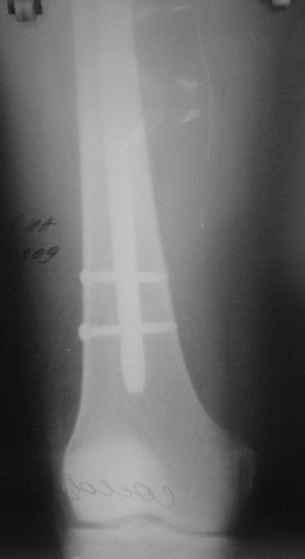

Сегодня прооперировали без открывания. Хотел-бы услышать комментарии по поводу послеоперационной нагрузки.

С уваженем, Ю.А.Булахтин

Учитывая изначальные снимки и то. что сделали , не открывая - весьма достойно. Доктор Коган прав - перелом немного перерастянут ( что хорошо видно по фибуле), а перерастянутые переломы большеберцовой срастаются очень плохо. Поэтому я бы обязательно дал раннюю динамизацию - на 6 неделях ( когда можно не опасаться малротации) разблокировал бы проксимальный фрагмент полностью и начал бы нагружать ногу. Будьте готовы к остеотомии ( или остеоэктомии участка) малоберцовой чеерз несколько месяцев- уж слишком хорошо стоит - очень вероятно, что срастется рано и будет держать большеберцовую перерастянутой

вдогонку - до разблокирования нагружать противопоказано - все, чего добьетесь - погнете шурупы. причем, если погнете дистальные ( как обычно бывает) - гвоздь провалится в сустав. Нагружайте птолько после проксимальной динамизации, когда будете уверены, что гвоздь поднагрузкой будет смещаться вверх, а не вниз

По представленым снимкам, "контакт" между отломками не очень =(. А боковой проекции нет?

Если "так оставлять", то время начала нагрузки мало повлияет на результат.

Уважаемый Юрий Алексеевич, сложный перелом, смелое решение, хорошее исполнение и, надо надеяться, хороший будет результат. Но, что бы он (результат) был достойным, надо подготовиться и к худшему. В чём, с моей точки зрения, главная проблема, которую придётся решать. Да, вне всякого сомнения, система нуждается в ранней динамизации в совокупности с ранней же нагрузкой. В данном случае, мне кажется, можно было бы решиться и на первичную динамизацию, то есть проксимально блокировать гвоздь только через овальное отверстие, отказавшись от введения винта через круглое отверстие. В этом случае и нагрузку можно было бы начать раньше, чем через 6 недель, не опасаясь перелома дистальных винтов. Однако, имеющееся лёгкое вальгусное смещение может прогрессировать в случае полной нагрузки, которую, как справедливо отмечено форумом, требует имеющееся стояние отломков. И предотвратить дальнейшее вальгирование может достаточная наружная опора, которая возможна при хорошем стоянии поперечного перелома малоберцовой кости даже без его внутренней фиксации, как раз как в представленном случае. А, в то же самое время, раннее сращение малоберцовой кости может препятствовать консолидации большеберцовой кости. То есть, своеобразный замкнутый круг может получиться. И так, главная проблема, с которой мы можем здесь столкнуться зависит не от диастаза между основными фрагментами, и не от вальгуса, и не от хорошей репозиции поперечного перелома малоберцовой кости - а от совокупности всех трёх факторов.

Поэтому, мне кажется, пациент будет требовать постоянного внимания на этапе реабилитации. И, помимо темпа консолидации, контроля положения дистального конца гвоздя из за опасения пенетрации сустава, не меньшего внимания будет заслуживать и угловое стояние отломков. Мне кажется, что в случае отсутствия формирования периостальной мозоли в допустимые сроки вряд ли будет целесообразным выполнение остеотомии малоберцовой кости. Это, равно как и хотя бы незначительное усугубление вальгуса может послужить основанием для переустановки гвоздя. Но - это худший вариант, который, я надеюсь, не случится. Но о котором нужно помнить.

АВ> Однако, имеющееся лёгкое вальгусное смещение

Что-то не то тут с вальгусом. По положению гвоздя не должно его быть.

Увидеть бы сравнительные снимки дистальных отделов голеней, может статься, симметричный голеностопный сустав выглядит так же.

Насчет диастаза - конечно, надо динамизировать хоть сегодня, ждать 6 недель я бы не стал. И боковой снимок бы увидеть.